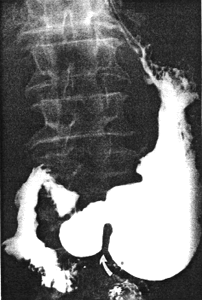

The great majority, if not all, cases of chronic, benign ulcers in the pyloric sphincteric cylinder are associated with contraction of the cylinder. In a recent series of 20 consecutive cases of gastric ulceration within 3.0 to 4.0 cm of the pyloric aperture, we noted contraction of the cylinder in all. The degree of contraction may vary from moderate (Fig. 29.5) to severe (Fig. 29.8), and will have a bearing on the radiographic appearance. Contraction of the cylinder implies diminished or absent cyclical activity of its musculature (Chap. 13) which, in turn, may delay emptying of solids and hamper trituration (Chap.18). In some cases contraction is associated with deformity of the cylinder (Fig. 29.6, 29.7). Cyclical activity is absent in these cases as well.